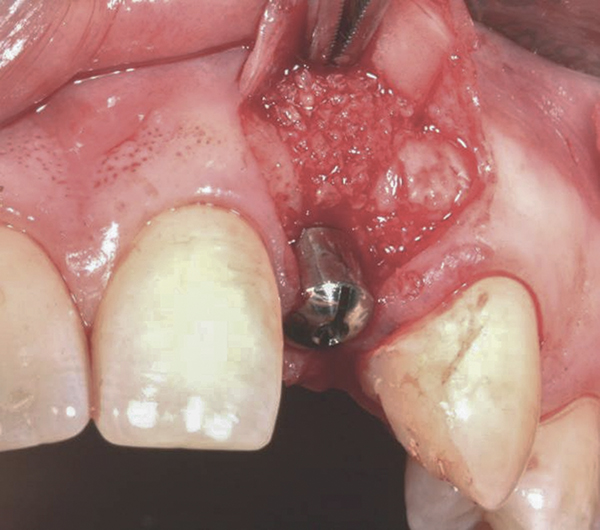

Fig 4. Implant inserted into the ridge, buccal view. There was a large labial concavity. The implant is seen on the buccal and terminates within the alveolar bone.

Figure 4